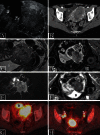

Although endometrial cancer is surgicopathologically staged, preoperative imaging is recommended for diagnostic work-up to tailor surgery and adjuvant treatment. For preoperative staging, imaging by transvaginal ultrasound (TVU) and/or magnetic resonance imaging (MRI) is valuable to assess local tumor extent, and positron emission tomography-CT (PET-CT) and/or computed tomography (CT) to assess lymph node metastases and distant spread. Preoperative imaging may identify deep myometrial invasion, cervical stromal involvement, pelvic and/or paraaortic lymph node metastases, and distant spread, however, with reported limitations in accuracies and reproducibility. Novel structural and functional imaging techniques offer visualization of microstructural and functional tumor characteristics, reportedly linked to clinical phenotype, thus with a potential for improving risk stratification. In this review, we summarize the reported staging performances of conventional and novel preoperative imaging methods and provide an overview of promising novel imaging methods relevant for endometrial cancer care.